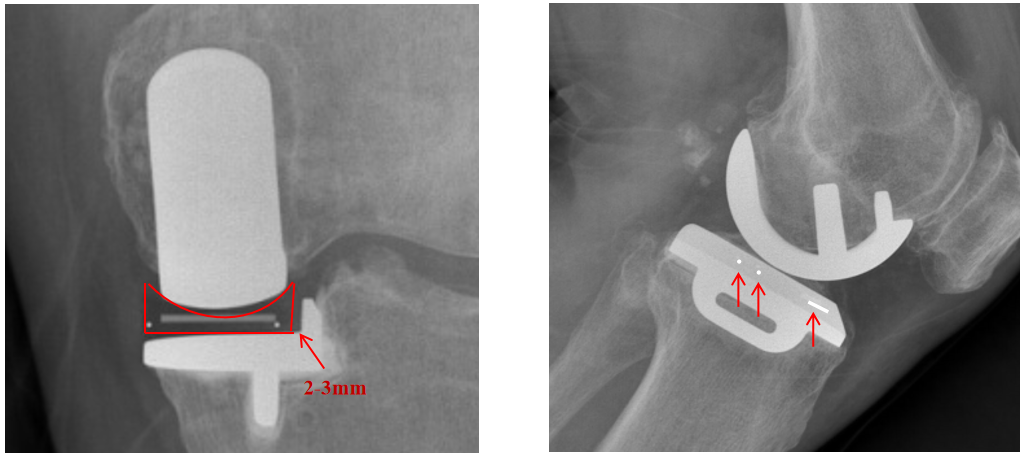

bearing前面有一条线,内外后角分别有一个小球。

在前后位片(AP),bearing在胫骨底板内外位置通过不透射线“—“和“. ”的标记推断出来。

Bearing的外侧面距离胫骨假体侧壁2-3mm(屈曲位时为1mm,伸直位胫骨发生了外旋)。

辨认bearing内的标识( X-ray正位)

bearing 内的标识:点和线段 “ .—. ” 线段显示为“—”在前;点显示为“.”在后

辨认bearing内的标识(X-ray侧位)

bearing 内的标识:点和线段“ .—. ”线段显示为“—”在前,点显示为“.”在后